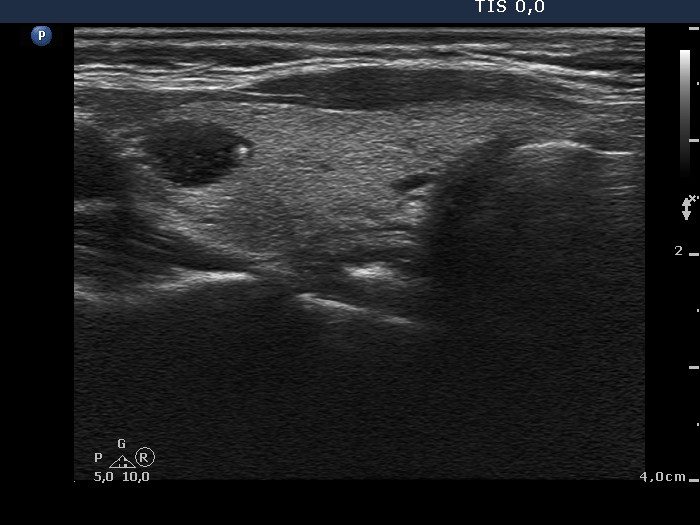

Benign nodular hyperplasia - Case 55. (ultrasonographic picture 7)

Left lobe, longitudinal scan. The hypoechogenic nodule contains a comet-tail artifact.